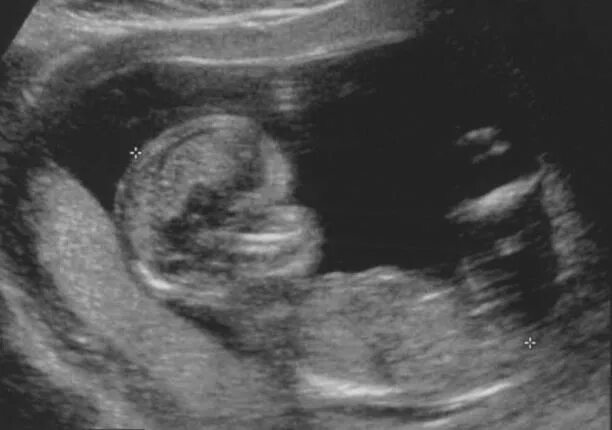

7 12 недель